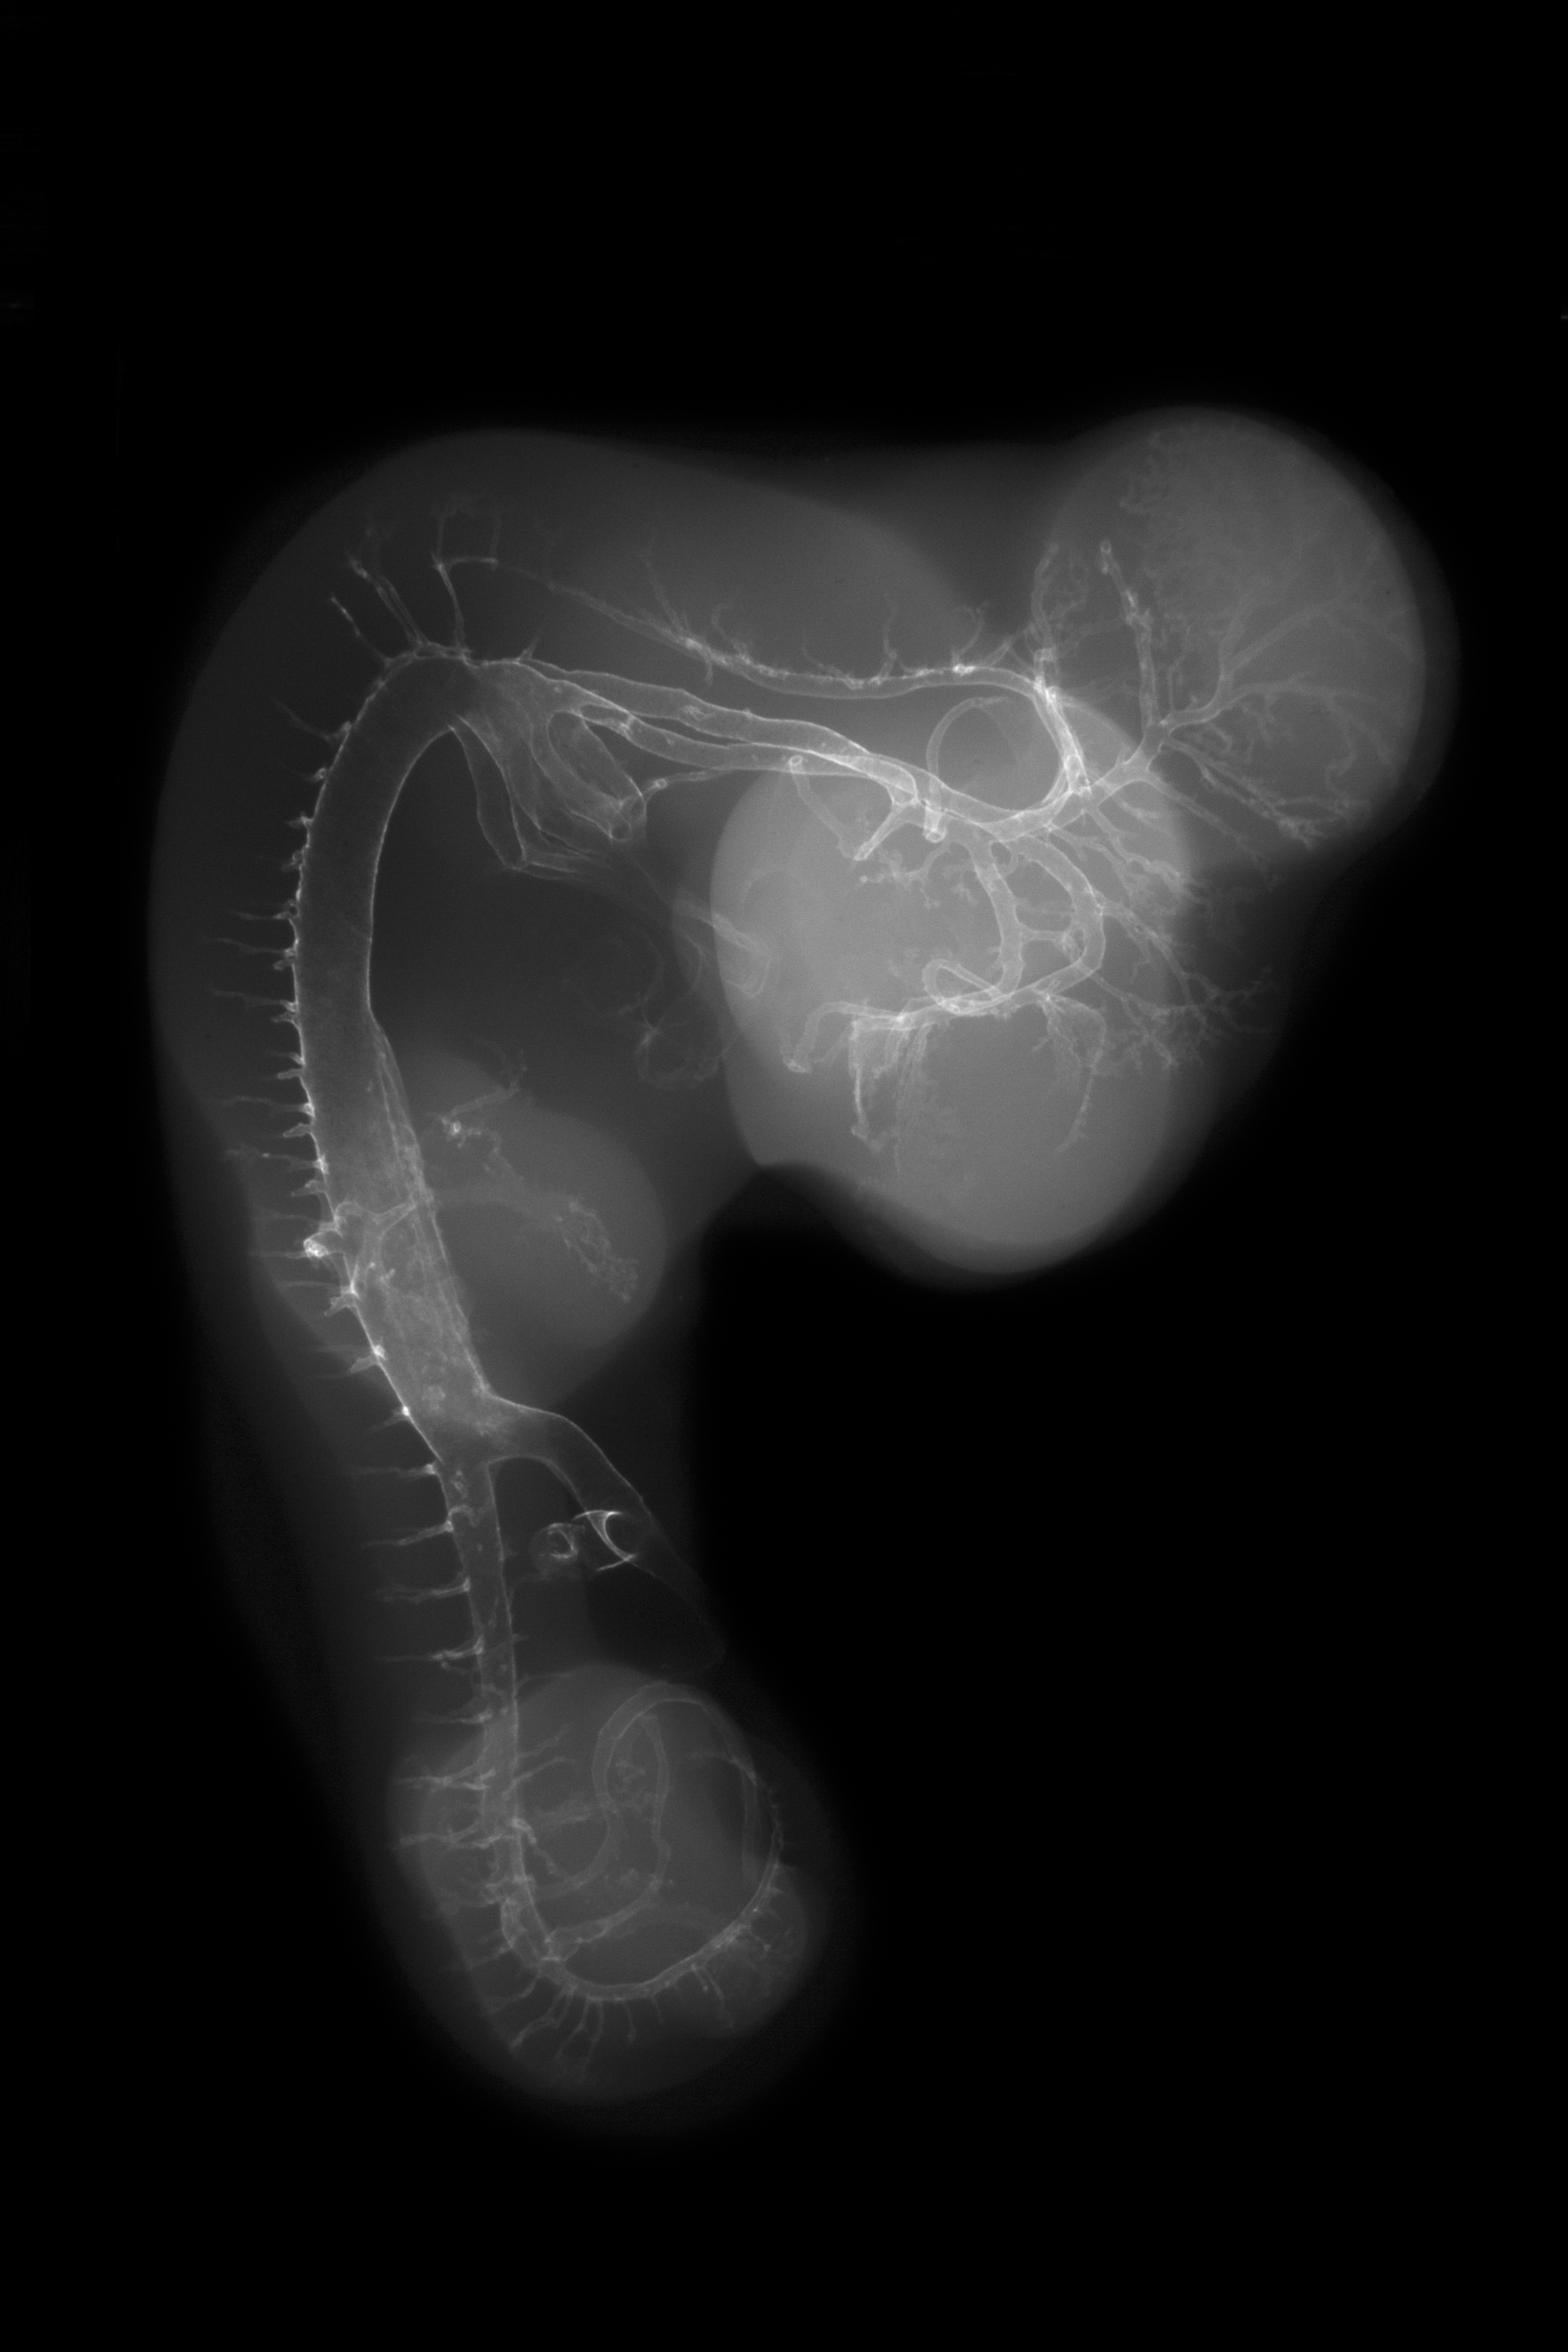

Chick Embryo Microangiography

Hamburger-Hamilton (HH) Stage 25 (approx. 4.5 - 5 days)

X-Ray Micrographs